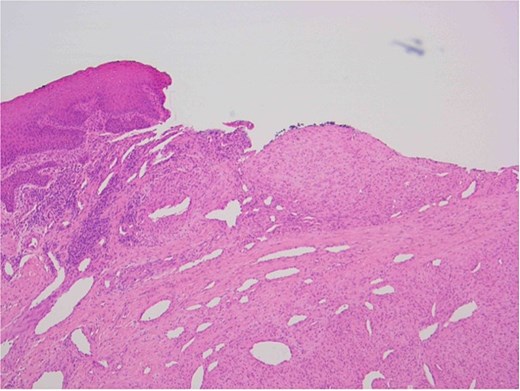

The patient underwent a biopsy of the lesion. Histopathological analysis revealed spindle cell proliferation arranged in a fascicular growth pattern, dilated hemangiopericytoma-like vessels, and a central myeloid nodule. Immunohistochemical staining was positive for smooth muscle actin (SMA), with no evidence of cellular atypia (Figs 5–7).

SMA immunostain showing diffuse positivity in spindle cells and highlighting myoid nodules.